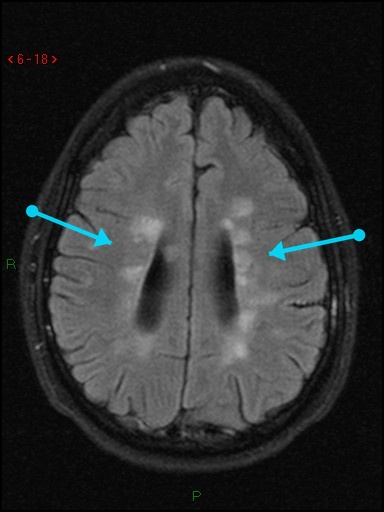

What's the Diagnosis?